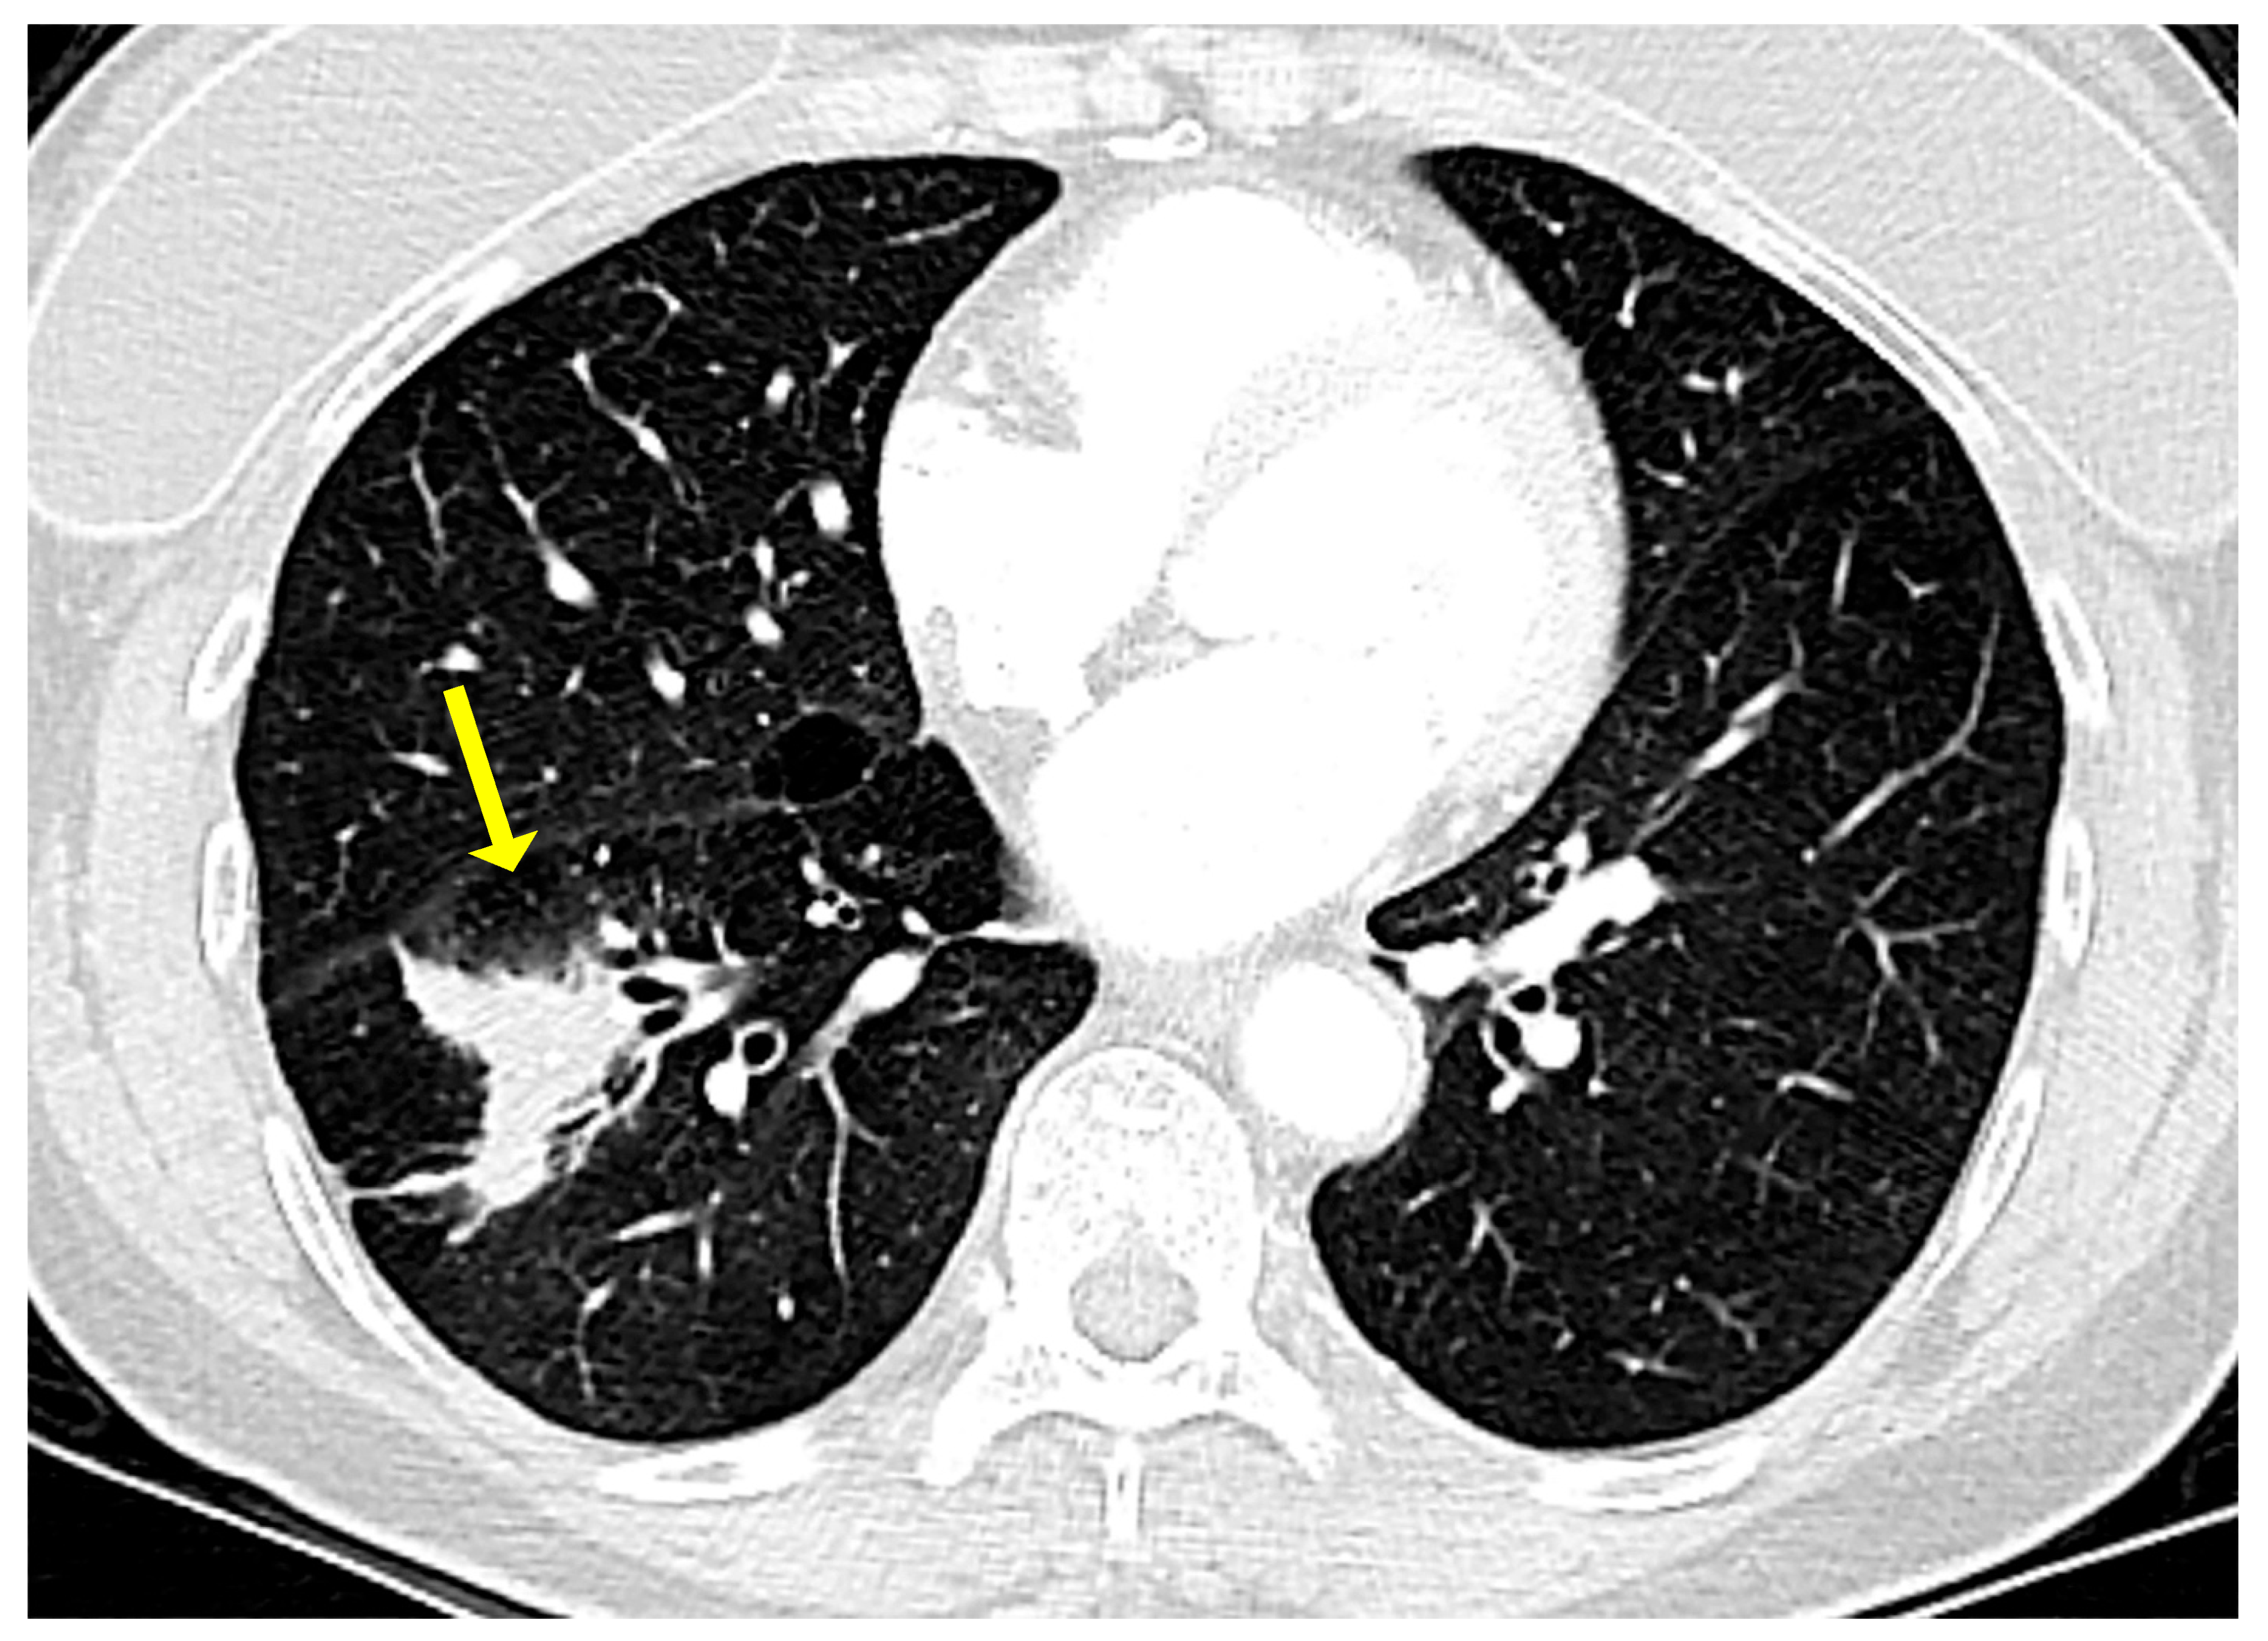

On a chest X-ray, pulmonary MALT lymphoma usually presents as a solitary lung mass. On high resolution computed tomography (CT) scan and magnetic resonance imaging (MRI), this lymphoma may present as a ground glass infiltrate with air bronchograms (Figure 1), as a peripheral mass with pleural thickening [8,9,10], or as consolidated lung parenchyma with air bronchograms and areas of apparent cavitation [11,12,13].

Figure 1.

Computed tomography in a case of pulmonary marginal zone lymphoma of mucosa-associated lymphoid tissue (MALT lymphoma). There is an ill-defined lesion in the right lower lobe originally thought to represent pneumonia (arrow). This lesion did not resolve with antibiotic therapy. Note the air bronchograms towards the medial aspect of the lesion.